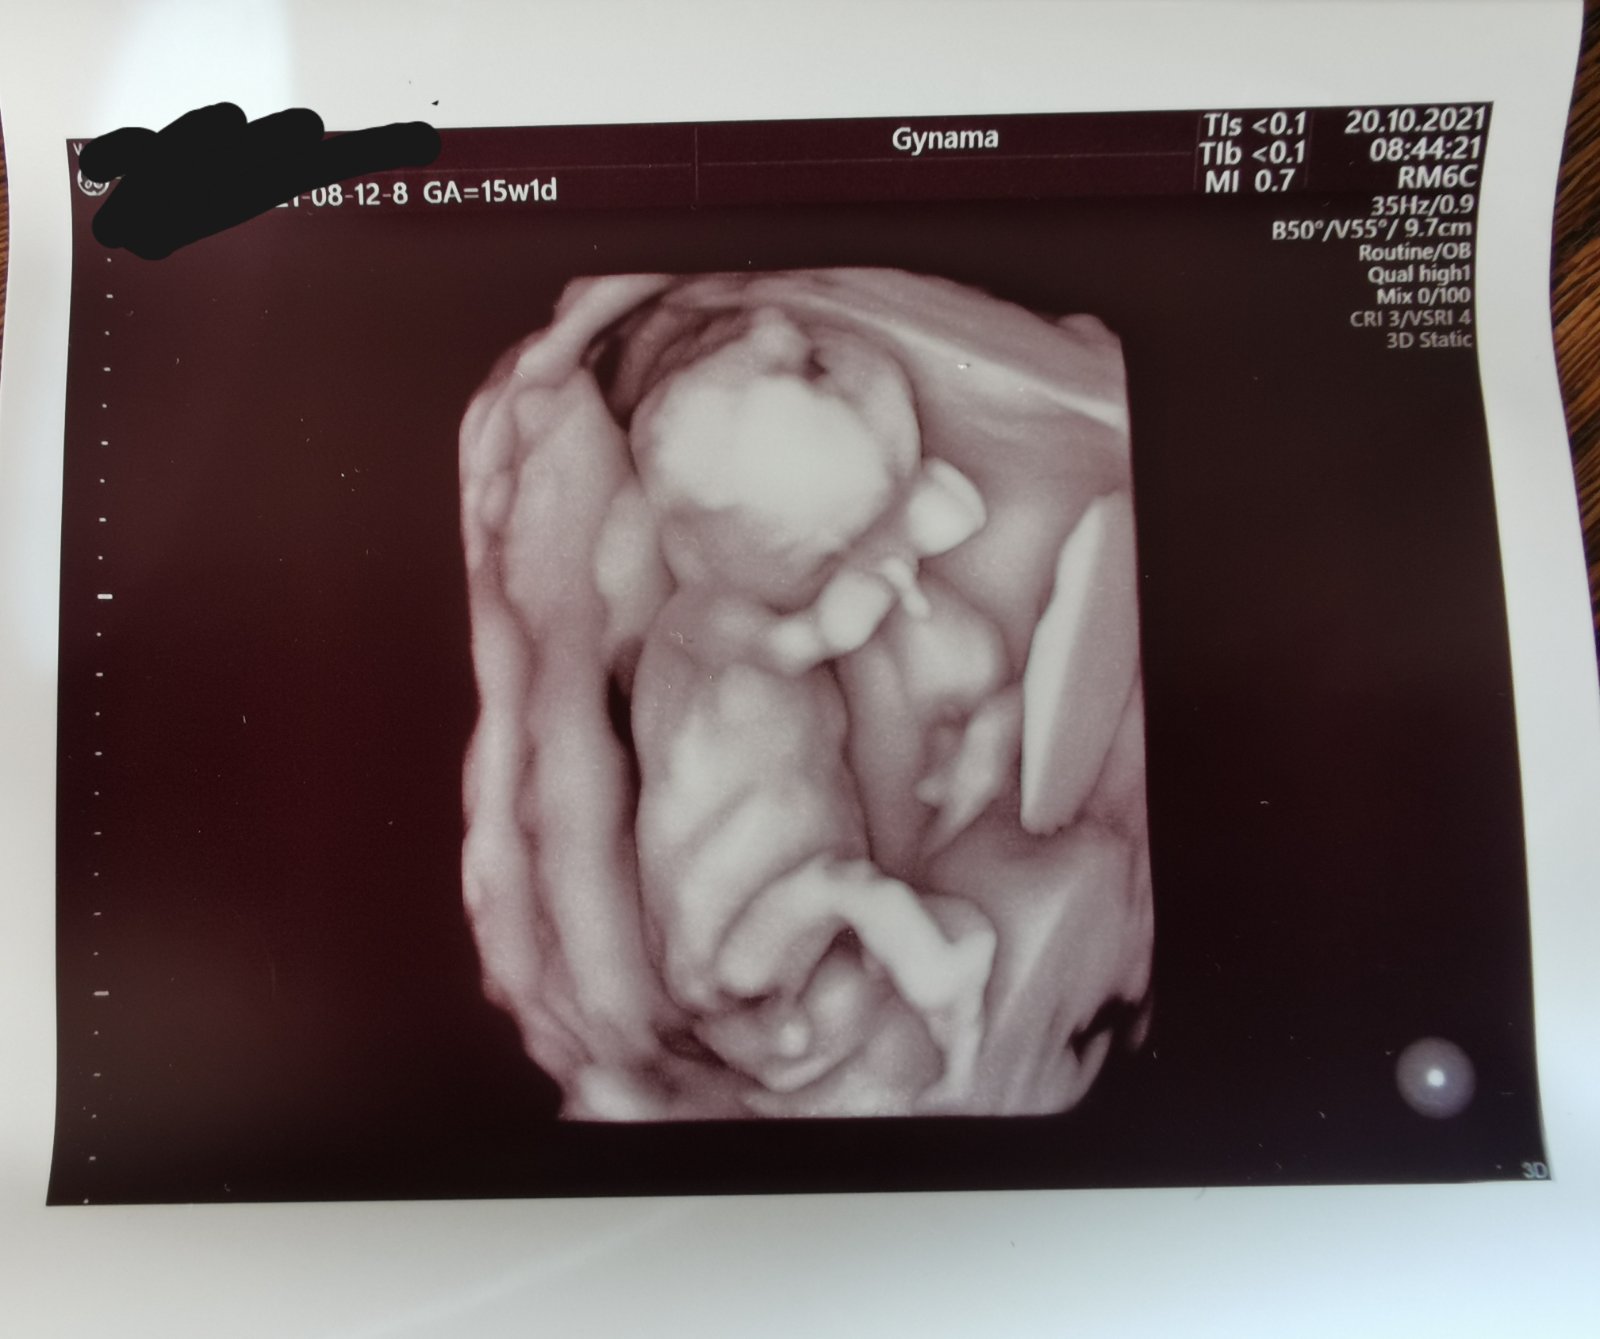

Ahojte, v 15tt+1 som bola na poradni, kde mi doktor robil aj sono a povedal mi, že to vidí pravdepodobne na dievčatko a spravil foto. Lenže je tam taký výbežok a ja som si neni istá a doteraz mi to vŕta hlavou. Na ďalšiu poradňu idem až v 20 týždni, takže ešte si chvíľu počkám na nejaké bližšie potvrdenie.

Ale povedzte, ako to vidíte vy? Takto to vyzerá naozaj na babu?🤔

Aj mne to pride ako chlapec, ale ten "výbežok " musel vidiet aj dr a keď mu to neprišlo ako pipik tak to bude asi dievča 😂

V tomto týždni je to ozaj ťažko predpokladať, ale vyzerá to ako formujúce sa kávové zrnko. Ale nie som lekár a hodnotím len podľa toho, čo som citala, keď som študovala v minulosti nasu fotku z ultrazvuku 🙂 a aj pre toto je lepšie informovať o pohlaví neskôr, lebo sa to zatiaľ dosť podobá 😂 pre porovnanie - tu je v 20tt chlapec - ma taku anténku 😃

v 15.tt je výbežok spoločný pre obe pohlavia, genitálie sa začnú formovať až neskôr...toto môže posúdiť naozaj len odborník... mne gynekológ v 12.tt povedal, že budem mať dcéru a mal pravdu, aj keď som si hovorila, že tom je snáď veľmi skoro na takéto tvrdenie... vysvetlil mi, že pohlavie určil podľa špecifického znaku v spodnej časti chrbtice, nie podľa genitálií ...netuším, o aký znak išlo, ale pohlavie mi určil so 100 % istotou, ani na sekundu nezapochyboval ...